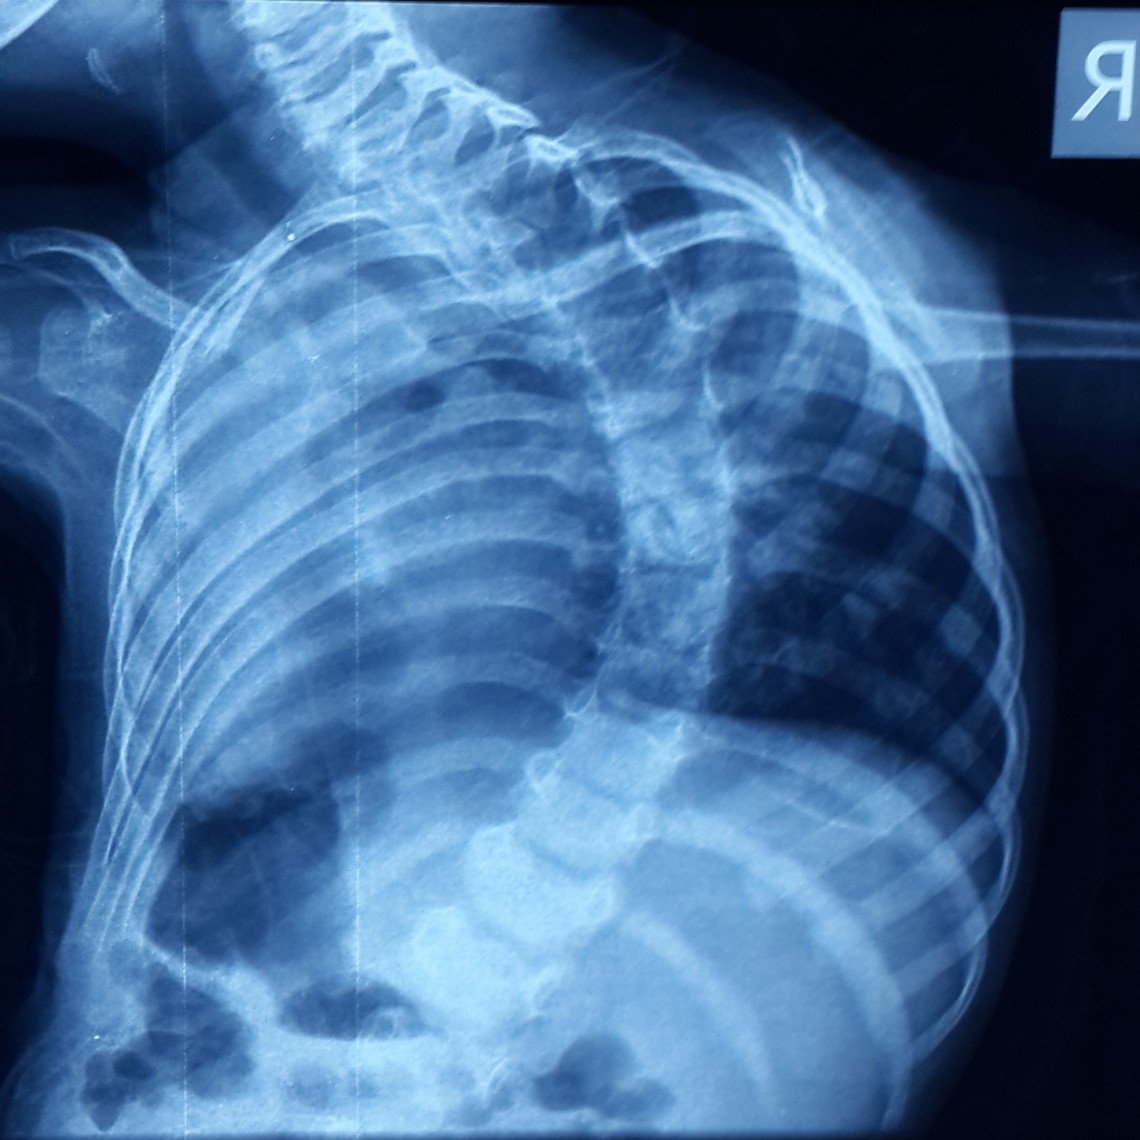

Farklı tipte skolyozu olan hastaların ameliyat öncesi ve sonrası fotoları: